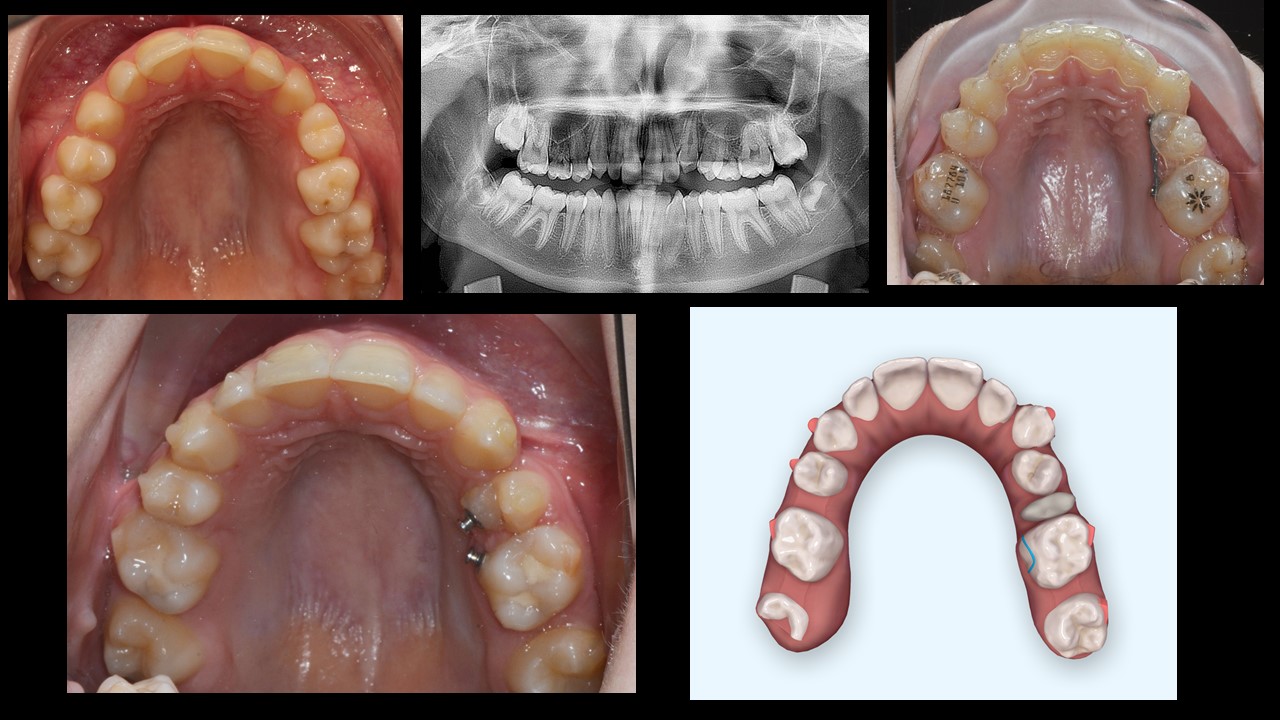

One of the main obstacles with clear aligners is rotation. As seen in this case, clear aligners which are combined with buttons on the palatal side will help to execute the rotation in a very short time.